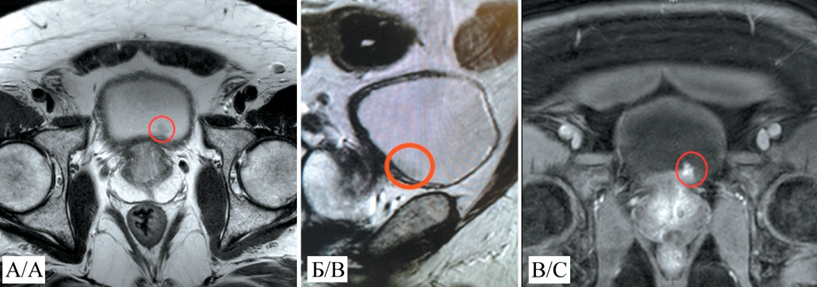

1. Рис. 1. МРТ органов малого таза с контрастированием: А – аксиальный срез, режим T1, опухоль выделена кружком; Б – сагиттальный срез, режим Т1, опухоль выделена кружком; В – аксиальный срез, режим Т2, опухоль выделена кружком. Примечание: рисунок выполнен авторами

Клиническое наблюдение. В урологическом стационаре ЧУЗ ЦКБ «РЖД-Медицина» Nd:YAG-лазерная абляция немышечно-инвазивного рака мочевого пузыря труднодоступной локализации проведена пациенту, 67 лет, с образованием по передней стенке МП. При гистологическом исследовании биоптата образования мочевого пузыря верифицирован рак мочевого пузыря. Поверхностный характер роста опухоли подтвержден по результатам магнитно-резонансной томографии, проведенной до операции. Для лечения применяли Nd:YAG-лазер с длиной волны 1 064 нм, мощностью 40 Вт и плотностью энергии 100 Дж/см2 . Лазерное излучение подавалось через световод с боковым выходом (Side Fire). После операции в МП установлен двухходовый катетер на 12 ч. Интра- и послеоперационных осложнений не было. Эндоскопический мониторинг эффективности хирургического этапа лечения проводился на базе ЧУЗ ЦКБ «РЖД-Медицина» с кратностью 3, 6 и 12 мес с момента операции, при этом признаков рецидива не обнаружено.